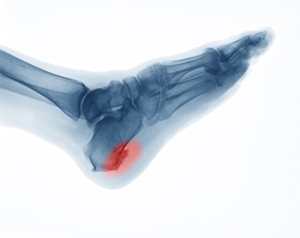

What Is a Heel Spur?

A heel spur is a bony calcium deposit that forms between the heel and the arch of the foot, often causing sharp pain, especially when standing or walking. Bone spurs commonly develop due to repetitive strain on the plantar fascia, which is the ligament that connects the heel to the toes. Risk factors include obesity, flat feet, high arches, poor footwear, and activities that place excessive stress on the feet, such as running or prolonged standing. Symptoms may include heel pain, inflammation, and difficulty walking comfortably. A podiatrist can diagnose heel spurs through examination and imaging, provide custom orthotics, recommend stretching and strengthening exercises, and discuss treatment options to relieve pain and restore mobility. If you have heel pain, it is suggested that you consult a podiatrist who can accurately diagnose what may be going on.

Heel spurs are formed by calcium deposits on the back of the foot where the heel is. This can also be caused by small fragments of bone breaking off one section of the foot, attaching onto the back of the foot. Heel spurs can also be bone growth on the back of the foot and may grow in the direction of the arch of the foot.

Older individuals usually suffer from heel spurs and pain sometimes intensifies with age. One of the main condition's spurs are related to is plantar fasciitis.

The pain associated with spurs is often because of weight placed on the feet. When someone is walking, their entire weight is concentrated on the feet. Bone spurs then have the tendency to affect other bones and tissues around the foot. As the pain continues, the feet will become tender and sensitive over time.

It is possible to have a heel spur without showing signs of any symptoms. However, if inflammation develops at the point of the spur’s formation, you may have pain while walking or running. In terms of diagnosis, sometimes all a doctor needs to know is that the patient is experiencing a sharp pain localized to the heel to diagnose a heel spur. Other times, an x-ray may be needed to confirm the presence of a heel spur.